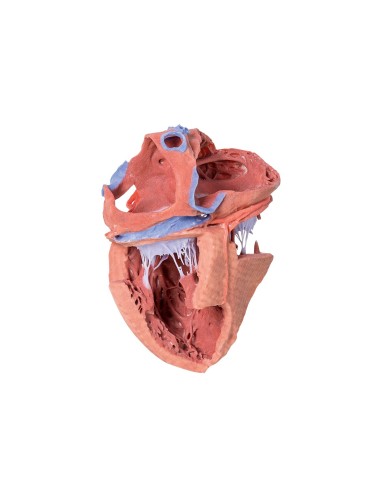

Modello di cuore di alta qualità scomponibile in 5 parti

Modello di cuore di alta qualità scomponibile in 5 parti

La parete anteriore del cuore è staccabile per poter vedere i ventricoli.

Realizzato in stampa 3D ad elevatissima risoluzione a colori.

Realizzato in stampa 3D ad elevatissima risoluzione a colori.

Realizzato in stampa 3D ad elevatissima risoluzione a colori.